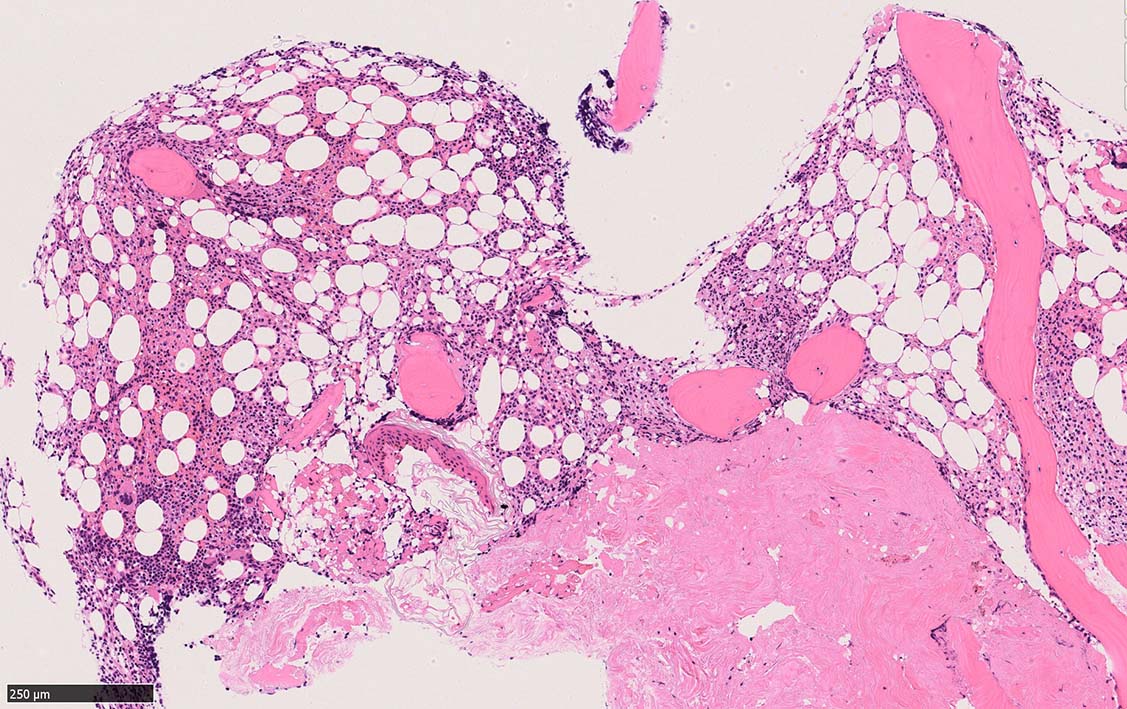

骨髄生検

bone marrow trephine biopsy: dry tapのため骨髄生検が行われる. cellularityは40-80%とhypercellular marrow. 流れのある細胞配列は線維化を疑わせる.